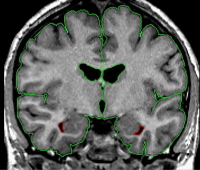

| General Description What we refer to as the inferior lateral ventricle (ILV) is actually the temporal horn of the lateral ventricle. This structure is located in the temporal lobe, and throughout its course it will change significantly in shape. The inferior lateral ventricle is extracted so as to exclude it from the hippocampus and amygdala outline; it is not considered a reliably extracted structure that is used for its own morphometric analysis. Most researchers combine the volume of the inferior lateral ventricle with what was previously described as the lateral ventricles when doing morphometric analysis on the lateral ventricles. Because of this, there are many methods that can be used to extract the ILV. |

|  | Anteriorly, the ventricle will appear more as a curved structure which follows the rounded lateral edge of the hippo-amyg area. Moving posteriorly the inferior lateral ventricle will comprise the border between the hippocampus and amygdala. Create an intensity contour line for the ILV. Your contour line will approximate the value of the lateral ventricles and/or the part of the tightened exterior that borders the hipp/amyg area. Once complete, extract this outline from the outside, and then the inside. It is also acceptable and more accurate to use a multiple-peaked histogram for the ILV, when accuracy is important. It is possible to draw one box that contains all three of the structures that make up the ILV borders (CSF, white matter, hipp/amyg), and then use the corresponding peaks to create the ILV outline. The first to second peaks will represent the CSF to hipp/amyg (gray) averaged intensity, and the second to third peaks represent the hipp/amyg (gray) to white matter averaged intensity. Use the "v" function to create the outline. |